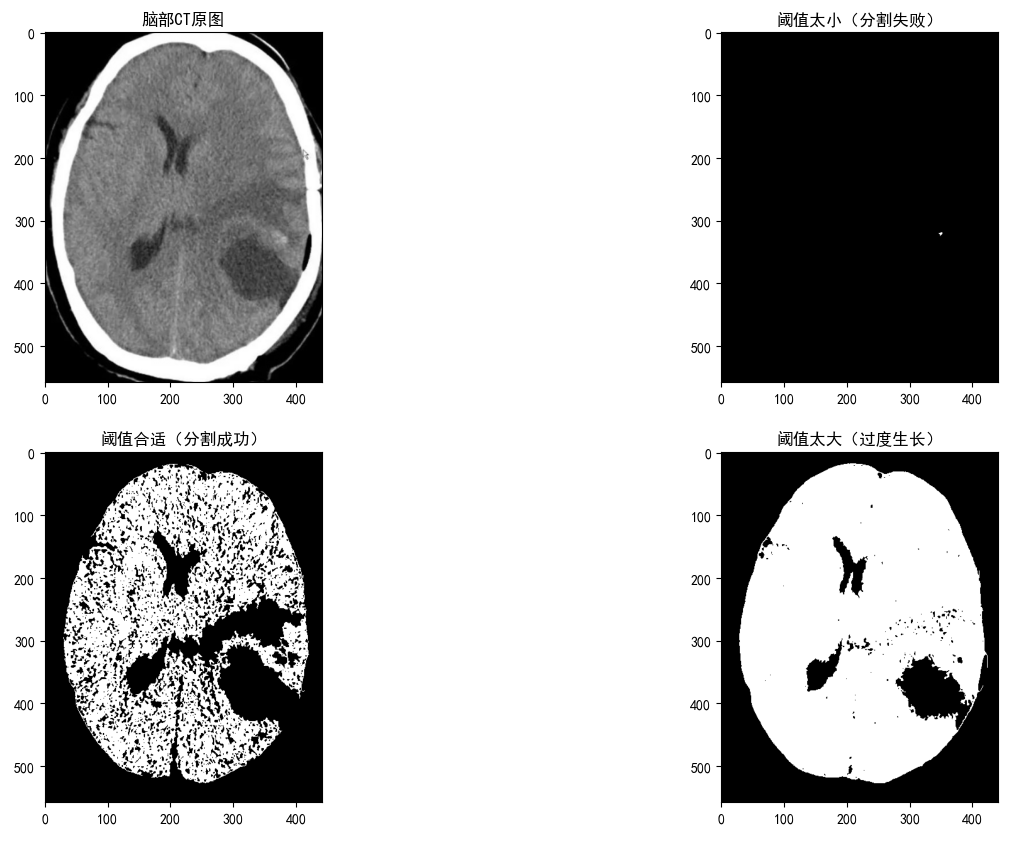

# 三种阈值效果

res1 = region_growing(img, seed, threshold=3) # 太小 → 几乎不长

res2 = region_growing(img, seed, threshold=15) # 正好 → 完美分割

res3 = region_growing(img, seed, threshold=40) # 太大 → 长过头

# 画图对比

plt.figure(figsize=(16, 10))

plt.subplot(2, 2, 1)

plt.imshow(img, cmap="gray")

plt.title("脑部CT原图")

plt.subplot(2, 2, 2)

plt.imshow(res1, cmap="gray")

plt.title("阈值太小(分割失败)")

plt.subplot(2, 2, 3)

plt.imshow(res2, cmap="gray")

plt.title("阈值合适(分割成功)")

plt.subplot(2, 2, 4)

plt.imshow(res3, cmap="gray")

plt.title("阈值太大(过度生长)")

plt.show()